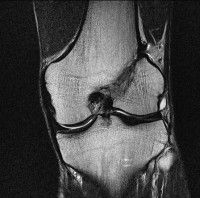

무릎 mri 간단히 봐주실 수 있으시나요 ㅠㅠ

안녕하세요 8년전 십자인대 수술하고 최근 무리한 운동에 무릎 불편감이 생겨서

mri 찍었습니다.

진단결과는 첫 찍은 병원에서 활액막염 이라는 진단을 받았습니다. 혹시 봐주실 수 있으실까요?

올라온 MRI가 단편적이라서 정확한 진단에 어려움이 있지만 십자인대에는 큰 이상이 있지는 않은것 같으며, 무릎관절내 물이 있는 것으로 보아 활액막염의 진단이 맞을 것 같습니다.

하지만 단편적인 영상이기 때문에 촬영병원에서 정확한 판독지 등을 받으시는 것이 좋겠습니다.